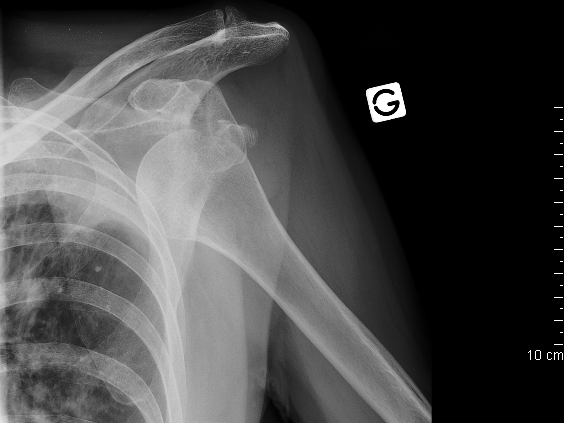

Omarthrose

Die Arthrose des grossen Schultergelenkes, sogenannt Omarthrose, macht sich glücklicherweise erst spät bemerkbar, da es sich im Vergleich zur Hüfte oder Knie kein tragendes Gelenk ist.

Das erste Zeichen einer Omarthrose sind häufig Bewegungseinschränkungen. Im Verlauf kommt dann der Schmerz.